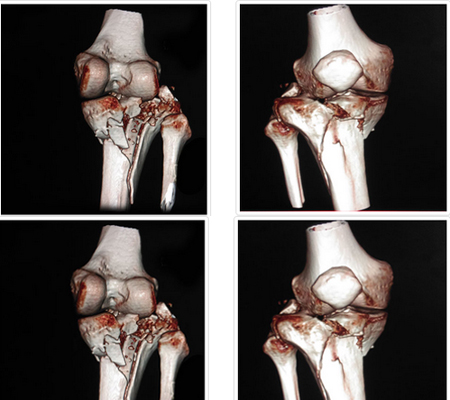

Complex Trauma Surgeries

Fractures and traumatic injuries happen unexpectedly. And while there's no way to prepare for such an injury, it's comforting to know you are in experienced hands. Our experienced surgeons are expert in handling Orthopaedic Trauma situations and perform minimally invasive surgery.

Trauma surgery is a surgical specialty which deals in trauma or accident related surgeries. It requires years of training in trauma surgery and critical care. Trauma surgeons are first required to stabilize the patient and then evaluating and managing the conditions of the patient. In our hospital, we have a trauma team which consist of health care professionals from all cadres like Orthopaedic Trauma Surgeon, General Surgeon, Neurosurgeon, Plastic Surgeon including nurses and support staff who understand that the needs of the trauma patients are very different from a planned surgery patient.

How are complex trauma fractures treated?

The management of fractures has improved considerably with excellent outcomes over the last few decades. These excellent outcomes can be obtained through early intervention by staying relatively active whilst keeping the fractured segment immobilised and subsequent rehabilitation to increase strength and range of motion.

Bespoke rehabilitation for each fracture based on patient and fracture characteristics are crucial for optimising the outcomes and to restore previous pre-injury levels. A collaborative multidisciplinary team (MDT) approach led by surgeons, anaesthetists, physiotherapist, occupational therapists, pain specialists, and patients themselves will ultimately lead to return to pre-injury activities of daily living, leisure, sport, and work.

May surgery be required to heal these complex injuries?

Orthopaedic injuries place the patient at risk for various complications, including fat embolism, pneumonia, deep vein thrombosis, and sepsis. Many studies have documented the benefits of early stabilization in reducing morbidity and mortality. Early definitive long bone fixation and external fixation methods have evolved and are considered an integral part of the initial care.

Innovative techniques like computer-assisted surgery continues to develop as technology improves. Uses in trauma include navigation for percutaneous screw placement in trauma surgery and for replacement surgery for reconstruction of complex fractures.

The ultimate target is to enable patients to return to their pre-injury levels. Surgery might be the only option in many of the complex trauma presentations. All these patients should be managed in a collaborative manner. Better understanding and identification of these injuries enables us to optimise the outcomes.